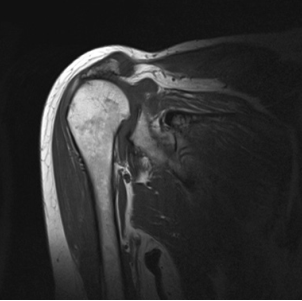

Meestal is aanvullend onderzoek nodig om de diagnose te bevestigen, zoals een röntgenfoto, echografie of MRI-scan.